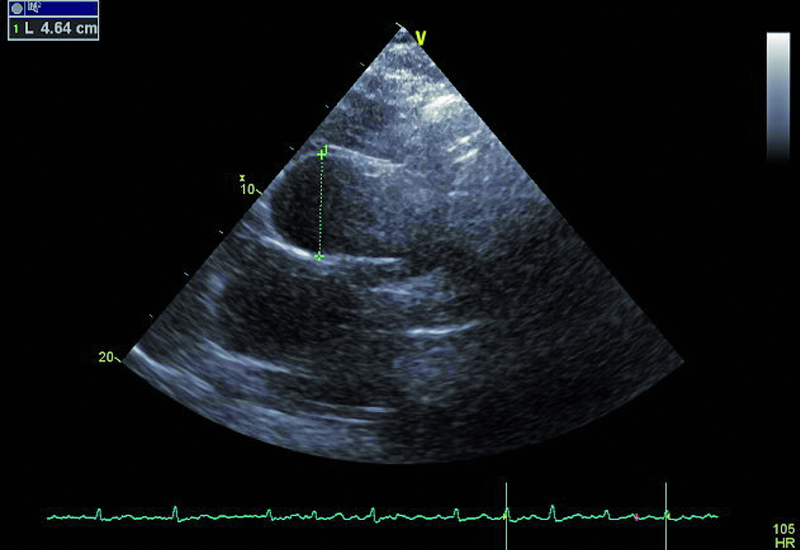

Kobieta, lat 73. Jakie patologie można rozpoznać na rycinach?

5. Poszerzenie prawej tętnicy płucnej (ryc. 3).